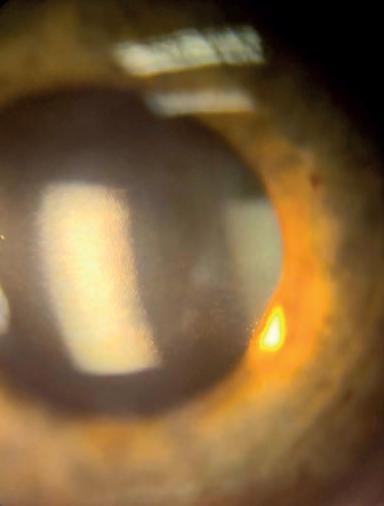

She said treatment with Syfovre is administered via intravitreal injections at fixed intervals between four to eight weeks, but unlike nAMD it would not likely be able to be individualised to alter the treatment interval.

In nAMD, most cases end up having anti-VEGF intravitreal injections, but Prof Guymer, who is on the international and local advisory board for Apellis, warned it would not be so straight-forward with GA.

“The decision to treat or not will be based on many factors relating to the actual GA lesion, the vision and AMD status in the eye, as well as individual circumstances.

Citing the OAKS and DERBY trials, Prof Fung said the rate of GA expansion can be reduced by about 20% over two years, following monthly or every other month Syfovre treatment. This benefit appears to increase the longer a patient stays on treatment. But two aspects needed to be considered when selecting patients, he said.

“Firstly, the patient needs to understand that this treatment can slow progression of their disease, but not stop or reverse it. They will not experience an improvement in their vision. Spending time educating patients on this aspect is critical to setting realistic expectations and maintaining treatment compliance,” he said.

“Treatment of GA with Syfovre is analogous to treatment of glaucoma with an intravitreal injection if there were no other available therapies. Patients should understand that the benefit of treatment needs to be weighed up against potential complications such as infection, inflammation or macular neovascularisation.”

needed to select eyes most likely to benefit. This should include eyes with AMD and not a masquerader of macular atrophy, such as an inherited retinal dystrophy.

“The GA should have been documented to progress on macular imaging. Eyes with extrafoveal, multifocal lesions, a ‘diffuse trickling’ pattern and associated reticular pseudodrusen grow the fastest and are most likely to benefit from this treatment.”

“They should be prepared to spend sufficient chair time, so that their patients are properly informed to decide for themselves if they wish to commence this new therapy,” he added.

Prof Andrew Chang, head of ophthalmology at the Sydney Eye Hospital and a vitreoretinal surgeon, said the challenge for eyecare professionals is how to screen, investigate and determine which GA patients would benefit most from long-term intravitreal injections of Syfovre.

“Patients and carers will need to be educated and supported to optimise compliance with therapy and manage their expectations of this new treatment,” he said.

“Clinicians are still learning about the disease and how to investigate the structure and function of the disease and how these correlate.”